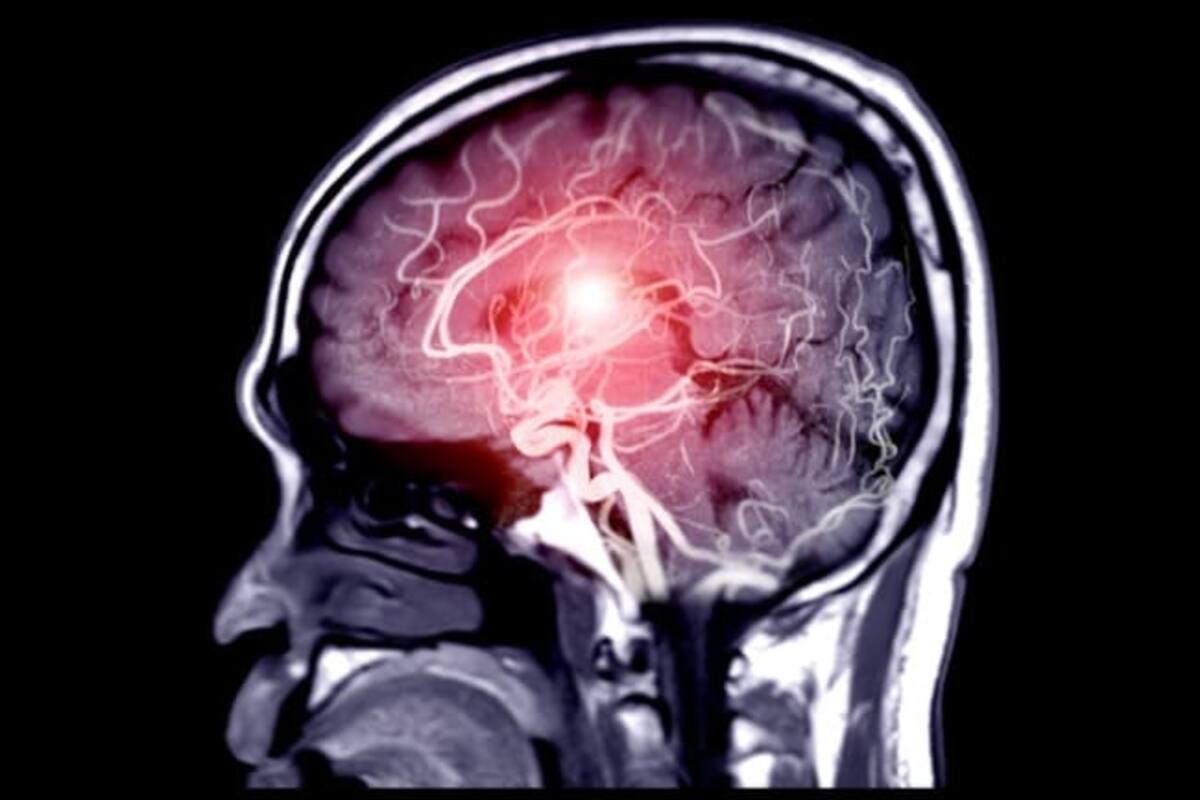

Según la investigación liderada por Naomi Thompson, la música actúa como una forma de estimulación cognitiva y sensorial, activando redes cerebrales que facilitan el acceso a recuerdos y emociones, incluso en personas con deterioro avanzado.